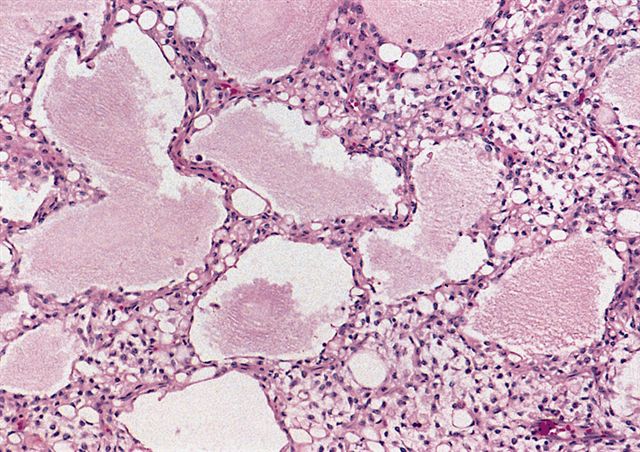

- Low grade

- Prominent plexiform vasculature (delicate thin walled arborizing and curving capillaries that form a network reminiscent of chicken wire fencing)

- These are striking because of the overall background paucicellularity and are still present in high grade tumors but are much less obvious

- Mucoid matrix is rich in hyaluronic acid that may form large mucoid pools (so called pulmonary edema pattern)

- Will be positive for stromal mucin stains such as Alcian blue (see Microscopic (histologic) images)